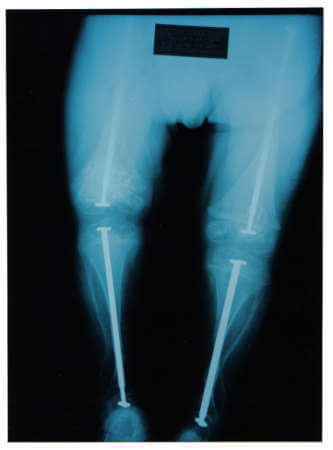

Εικόνα αντιμετώπιση με εκπτυσσόμενους ήλους

Η χειρουργική διόρθωση είναι η διόρθωση του άξονα με πολλαπλές οστεοτομίες και ενδομυελική ήλωση με ειδικούς εκπτυσσόμενους ήλους εν είδη κεραίας ραδιοφώνου.

Οι ήλοι καθηλώνονται στις επιφύσεις και εκπτύσσονται με αύξηση του μήκους των άκρων, διατηρώντας το φυσιολογικό άξονα και δρώντας στηρικτικά στο οστούν, ώστε να μην υπόκειται εύκολα σε κατάγματα.